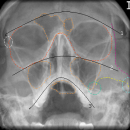

Nasennebenhöhlen (NNH)

CAVE

• Knöcherne Konturen der Sinus

• Spiegelbildung und/oder Verschattungen in den Sinus (Hämatosinus)

• Konfiguration der Apertura piriformis

• Konturlinien nach Dolan: Orbitarandlinie, Jochbein-Jochbogenlinie, Maxilla-Jochbein-Linie

• Bogenlinien nach McGrigor und Campbell:1 Supraorbitalbogen, 2 Infraorbitalbogen, 3 Zahnreihe

Indikation

• V.a. infrazygomatikale Frakturen

• V.a. Zentrale / zentrolaterale / laterale Mittelgesichtsfraktur

• V.a. craniofaziale Fraktur

• V.a. panfaziale Frakur

Mittelgesichts-CT empfohlen